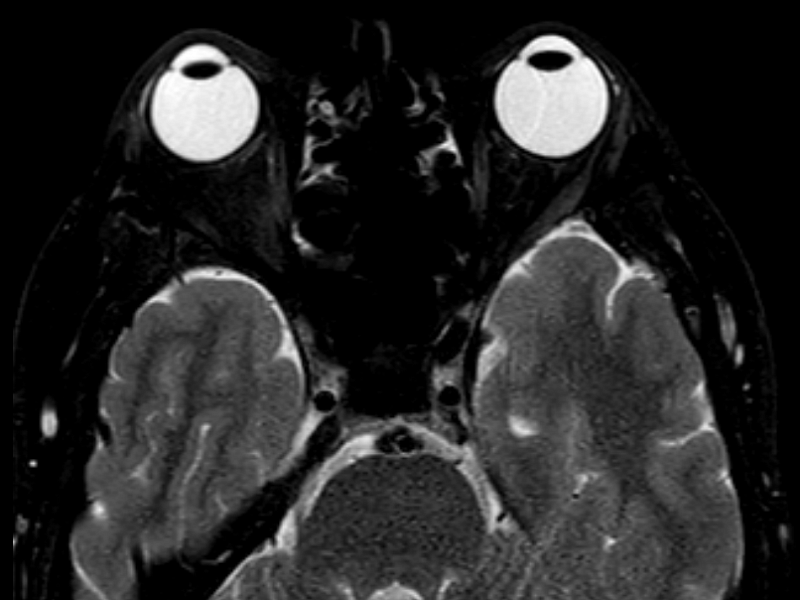

Магнитно-резонансная томография орбит – важный метод исследования, который позволяет оценить структуры орбит.

Как проводится МРТ орбит?

Перед укладкой в томограф необходимо снять все металлические предметы. После этого пациент ложится на стол сканера, который постепенно перемещается в аппарат. Во время сканирования следует лежать неподвижно, чтобы получаемые изображения были четкими и неискаженными.